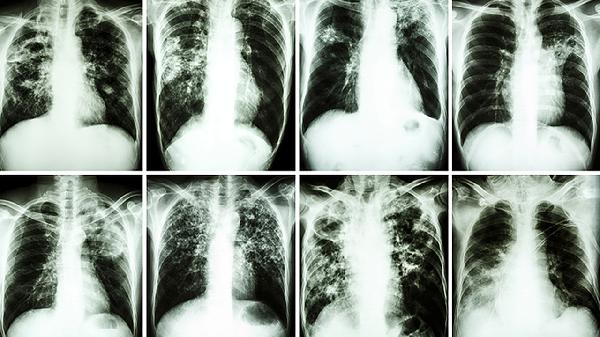

4、频繁感染:血癌患者的免疫功能受损,容易发生反复感染。建议保持良好的个人卫生习惯,避免接触感染源,必要时可使用免疫增强剂或抗生素预防感染。

6、淋巴结肿大:血癌患者常出现颈部、腋下或腹股沟等部位的淋巴结肿大。建议进行超声或CT检查以明确肿大原因,必要时进行淋巴结活检以确诊。